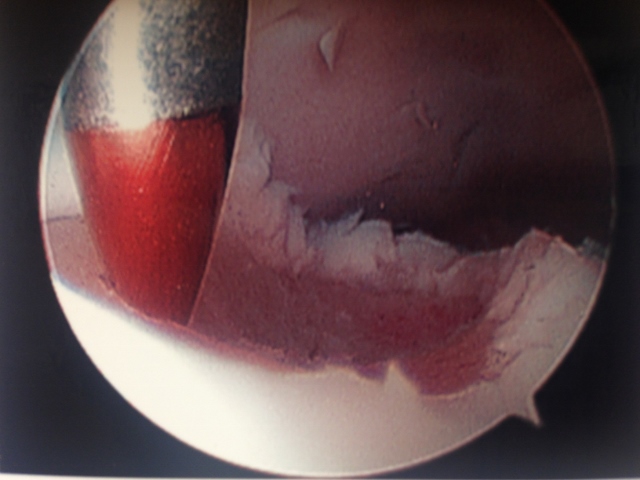

Action shot of microfracture of talus OCD.

Bleeding of OCD after microfracture.